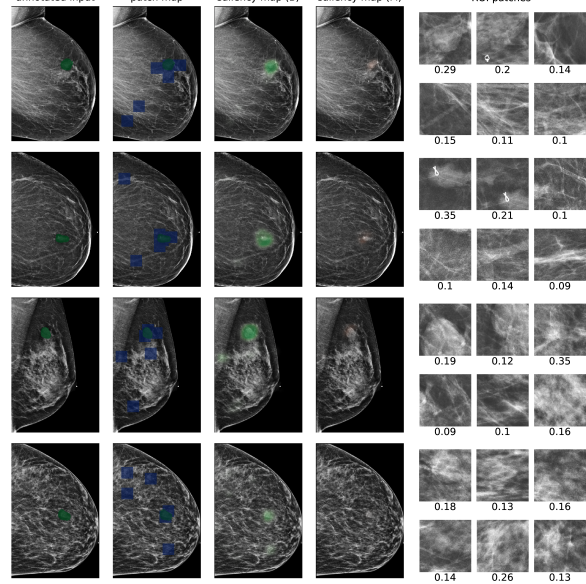

In Figure 7, we visualize saliency maps for four samples selected from the test set. In the first two examples, the saliency maps are highly activated on the annotated lesions, suggesting that our model is able to detect suspicious lesions without pixel-level supervision. Moreover, the attention is highly concentrated on ROI patches that overlap with the annotated lesions. In the third example, the saliency map for benign findings identifies three abnormalities. Although only the top abnormality was escalated for biopsy and hence annotated by radiologists, the radiologist’s report confirms that the two non-biopsied findings have a high probability of benignity and a low probability of malignancy. In the fourth example, we illustrate a case when there is some level of disagreement between our model and the annotation in the dataset. The malignancy saliency map only highlights part of a large malignant lesion with segmental coarse heterogeneous calcifications. This behavior is related to the design of : a fixed pooling threshold cannot be optimal for all sizes of ROI. The impact of is further studied in 3.6. This example also illustrates that while human experts are asked to annotate the entire lesion, CNNs tend to emphasize only the most informative regions. While no benign lesion is present, the benign saliency map still highlights regions similar to that in the malignancy saliency map, but with a lower probability than the malignancy saliency map. In fact, calcifications with this morphology and distribution can also result from benign pathophysiology [42].